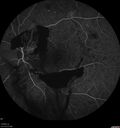

44 year old man About 2 months ago, the patient went to the beach with his family and noticed a hair in the eye sight in the left eye.  He was trying to rinse it out and saw that there was something not right.  He googled the problem and there was something about a floater and not being a big deal.  His vision was pretty good.  He was not getting regular eye examinations.  He did get checked in 2015 and got new glasses.  He had not been back since then for the last 5 years except for glasses. Last week the vision in the left eye got bad.  The vision in the right eye is fine.   VA OD: sc20/40 PH20/25 NscJ2 VA OS: sc20/63-2 PH20/32-1 NscJ1 IOP: TP: OD:17 OS:19

Proliferative Diabetic Retinopathy and vitreous hemorrhage left eye330 views44 year old man with type II diabetes for 14 years and no eye examinations in the last 5 years. VA 20/40 right eye and 20/60 left eye. Vision loss has been for about a week in the left eye.00000